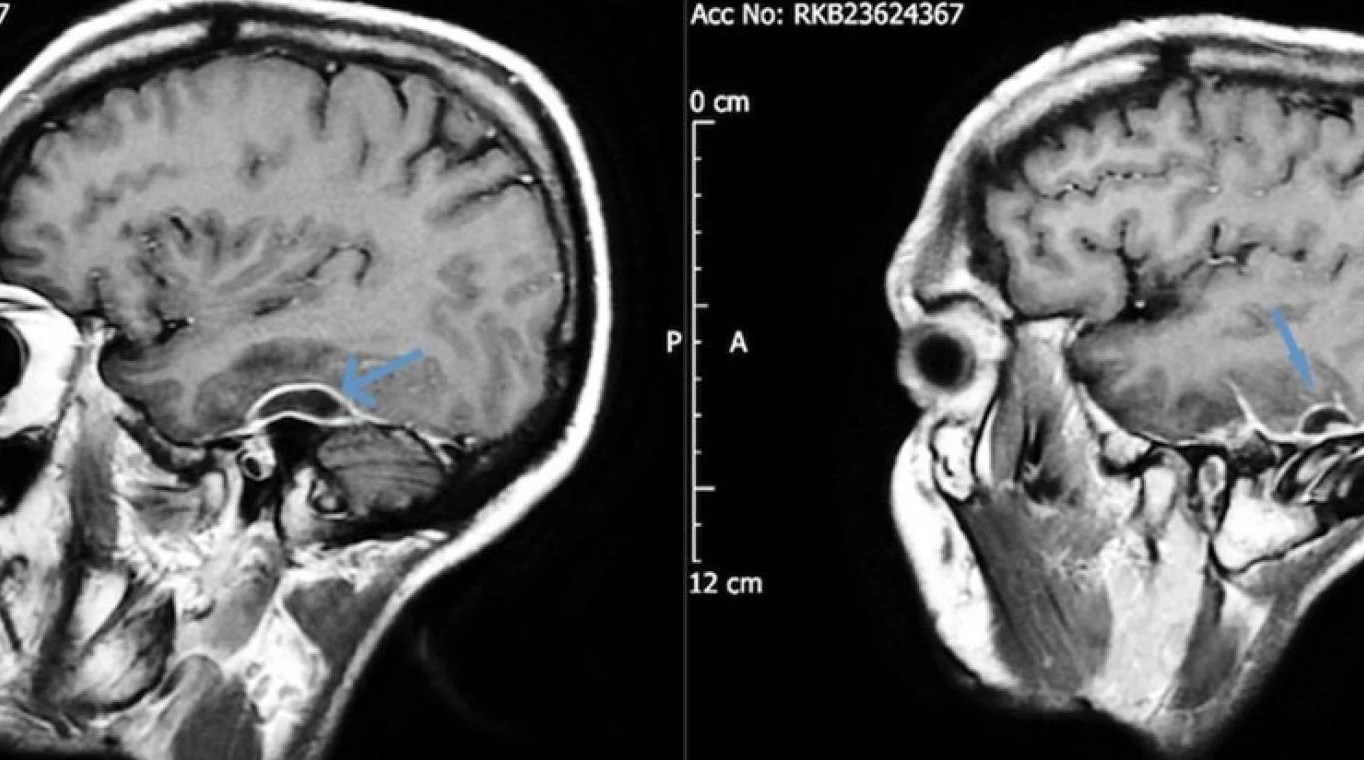

Desde el servicio de emergencias pidieron una tomografía de cabeza y encontraron en el paciente acumulaciones de pus en el tejido que rodeaba su cerebro. Los análisis de sangre revelaron que la bacteria que causó la grave infección fue la Pseudomonas aeruginosa, y se trasladó a través de un pedazo de algodón que formaba parte de un hisopo que se había desprendido dentro de la cabeza del paciente hacía años. La infección, también conocida como otitis externa necrosante, podría afectar los nervios faciales, causando secuelas similares a las de un accidente cerebrovascular. Sin embargo, en este caso y a partir del descubrimiento, se procedió a retirar el algodón con anestesia y después de ocho semanas de antibióticos intravenosos, el hombre se recuperó por completo.